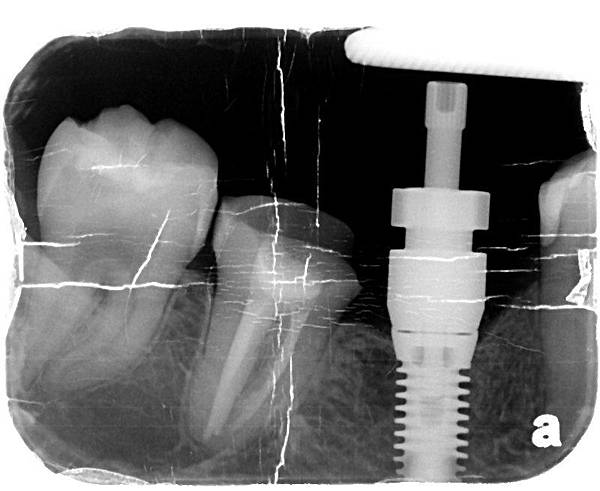

X光片系列

X光片系列

完成圖 X光片系列

X光片系列